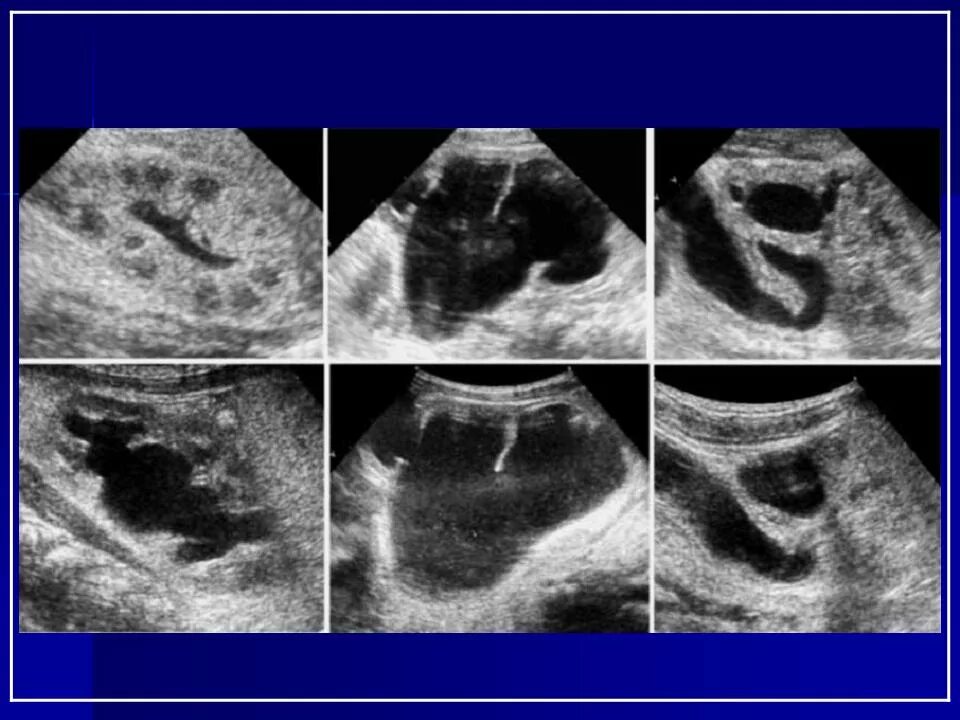

Узи аномалий